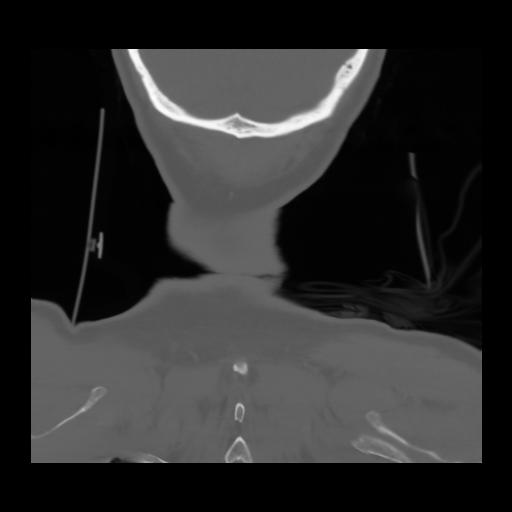

13 P.BLANDAS,,Coronal,2.000,P.BLANDAS,Coronal,